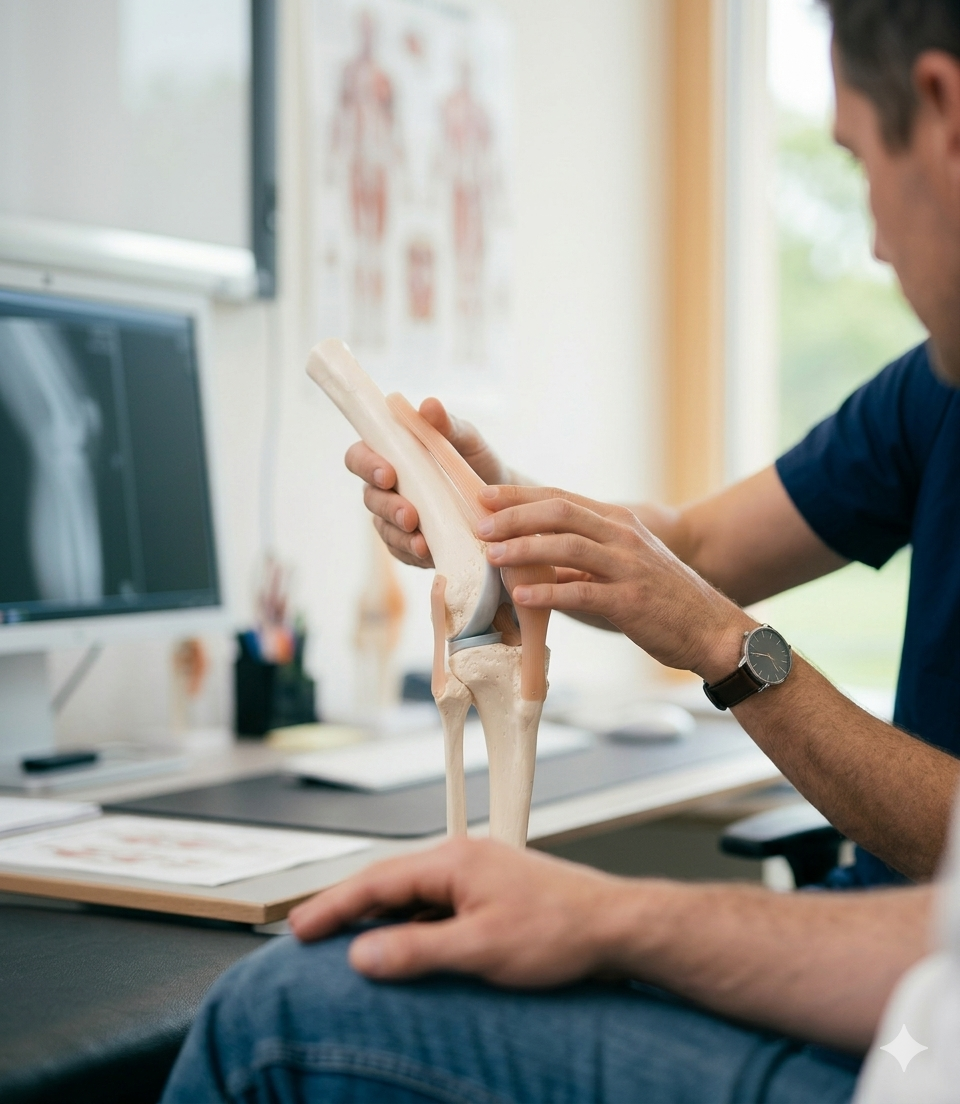

Chirurgie du genou ligamentaire et prothèse (PTG)

Chirurgie ouverte et arthroscopique, prothèse planification 3D